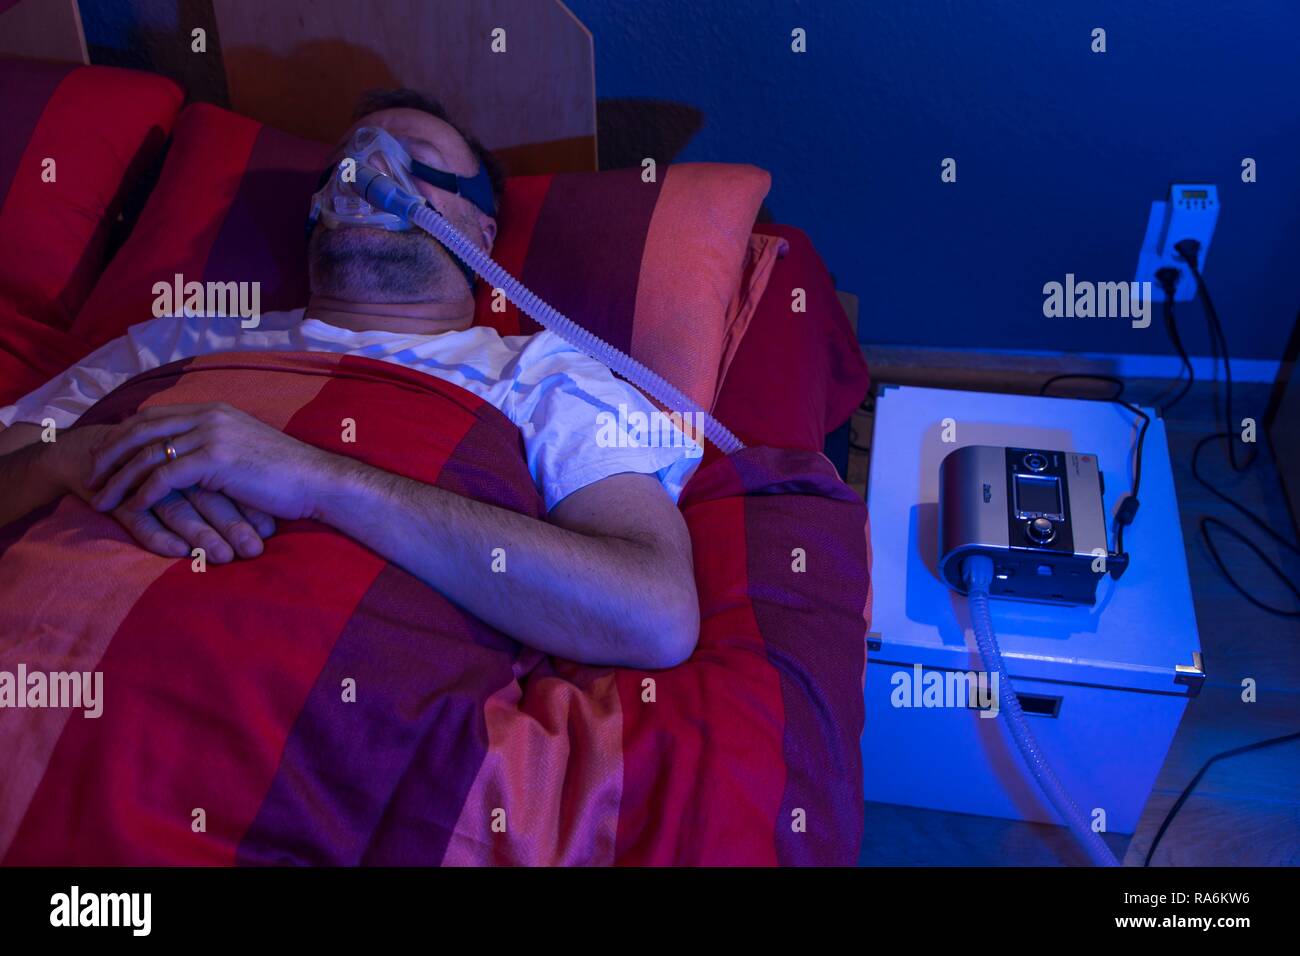

Man with sleep apnea syndrome, wears a CPAP mask while sleeping, breathing mask, which pushes air into the respiratory tract due Stock Photohttps://www.alamy.com/image-license-details/?v=1https://www.alamy.com/man-with-sleep-apnea-syndrome-wears-a-cpap-mask-while-sleeping-breathing-mask-which-pushes-air-into-the-respiratory-tract-due-image230028658.html

Man with sleep apnea syndrome, wears a CPAP mask while sleeping, breathing mask, which pushes air into the respiratory tract due Stock Photohttps://www.alamy.com/image-license-details/?v=1https://www.alamy.com/man-with-sleep-apnea-syndrome-wears-a-cpap-mask-while-sleeping-breathing-mask-which-pushes-air-into-the-respiratory-tract-due-image230028658.htmlRMRA6KW6–Man with sleep apnea syndrome, wears a CPAP mask while sleeping, breathing mask, which pushes air into the respiratory tract due